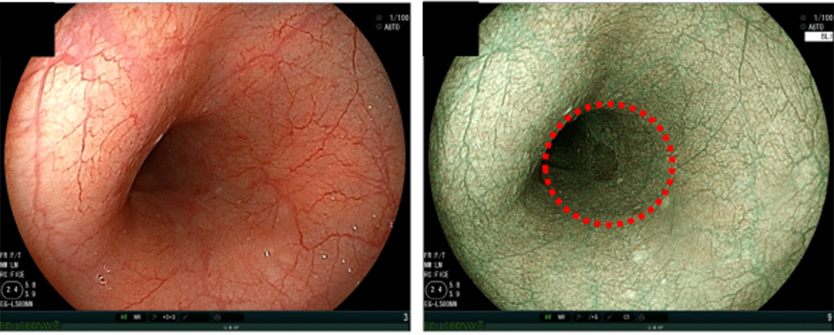

画像強調により、診断がより簡単に

レーザー内視鏡には、光の強度や映し出した胃の中の色調を調整する機能がついており、それによってより病気の観察がしやすくなっております。

より細やかな色の変化を映し出したり、長い距離で血管や表面構造を強調させスキャンすることや、粘膜の血管をより浮かび上がらせた画像を作ることができます。

これにより、病気の発見だけでなく診断も簡単になり、患者さんからみてもより症状がわかりやすくなっております。